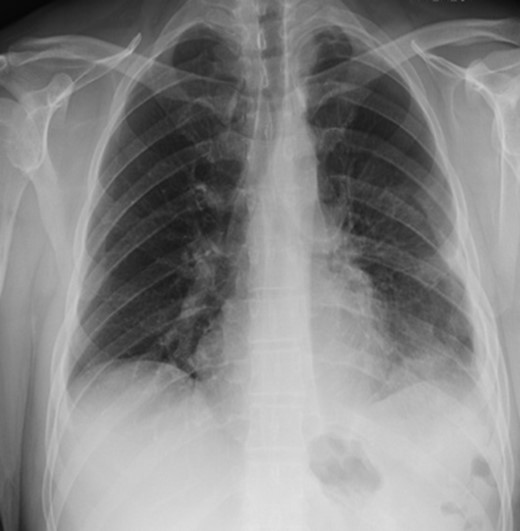

We present a 44-year-old male patient came to the emergency department complaining of right upper quadrant abdominal pain. The patient reported taking over-the-counter (OTC) ibuprofen intermittently for a past few months due to backaches. His past medical history is only positive for falling off a 15 feet ladder at the age of 15 years old. Upon examination, he had right upper quadrant abdominal tenderness, a heart rate of 90 beats/min and a respiratory rate of 20 breaths/min on room air. The patient clinical status was stable and looked well. Chest x-ray showed a moderate left hemidiaphragm elevation with bowel contents overlying the left chest (Fig. 1). Of note, a large amount of air inferior to the right hemidiaphragm was indicative for pneumoperitoneum. Laboratory investigations were immediately carried out and revealed a white blood cell count (WBC) of 4.5 × 109/L (normal range: 4–11 × 109/L). The WBC remained at the normal level until the end of the patient’s admission. Further imaging studies were ordered due to the peculiar coexistence of x-ray findings and stable clinical status. The computed tomography (CT) scan showed a contracted left lung with severe volume loss and just mild aeration of the left upper lung (Fig. 2). No definite left pneumothorax was seen. The majority of the left hemithorax was filled with abdominal contents including the stomach, spleen, pancreatic tail, left kidney, splenic flexure of the colon, and small bowel loops. A small hypodense focus was observed within the intra-thoracic stomach and extended to the stomach wall, with mild adjacent stranding of fat and a small amount of free fluid. We suspected the presence of perforated gastric ulcer secondary to non-steroidal anti-inflammatory drugs (NSAIDs) usage. The upper gastrointestinal (GI) series was performed and did not show any extravasation, indicating that there was some other source or the gastric perforation had walled off. The patient was thus managed conservatively; his diet was advanced and the patient discharged home on Day 4.

Chest x-ray showed a moderate left hemidiaphragm elevation with bowel contents overlying the left chest.